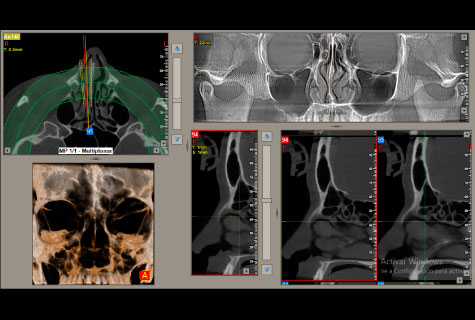

Contamos con un equipo tomográfico dental de los más modernos del país con tecnología de ultima generación para obtener magníficos resultados con una excelente calidad de imagen.

Tomografía Cone Beam

- Tomografía Macizo Facial

- Tomografía senos paranasales